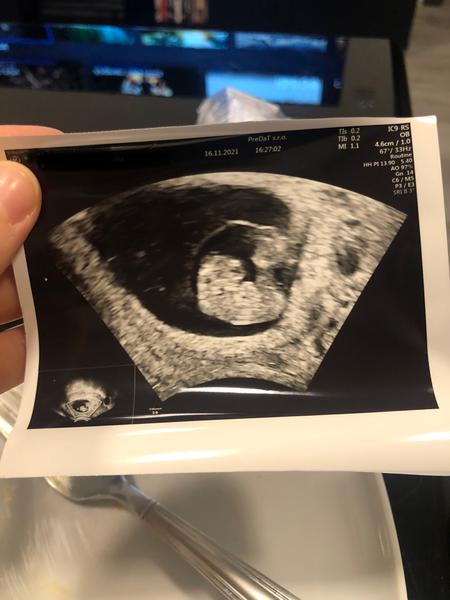

@kristousenecek my dnes začínáme 9 týden ❤️🍀